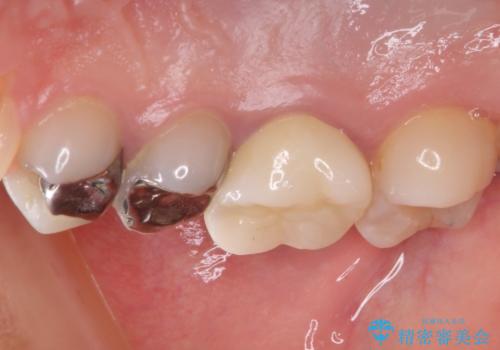

- 笑ったときに見てしまう上顎奥歯の銀歯を気にして来院された患者様です。

折角セラミッククラウンを装着するので、根管治療を行った後に補綴治療を行うこととしました。

他にも目立つ銀歯がありましたが、最も気にしている2本を優先して行うこととしました。

結婚式前にはクリーニングやホワイトニングを行い、その後他の歯を治療していく予定です。